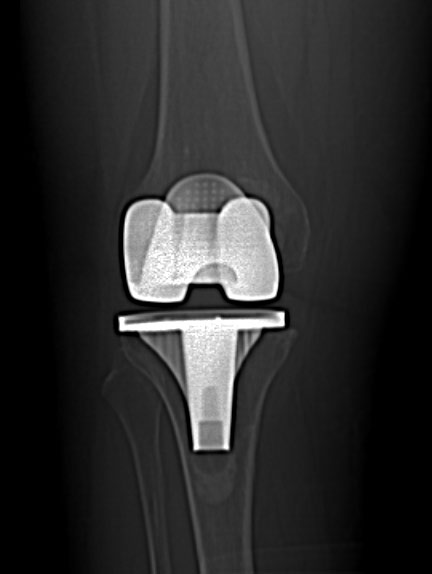

Afișarea cu evidențierea părților moi sau ale osului

De obicei, pentru articulatii/ oase, se folosesc imagini cu doua tipuri de parametri diferiti: pentru parti moi si pentru os.

Reconstrucții în alte planuri (MPR)